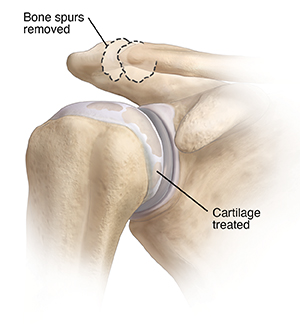

Arthritis and loose bodies

Arthritis is damage to joint cartilage with age and use. Injury or disease can also cause it. Wear and tear may also lead to loose bodies (pieces of bone or cartilage) or bone spurs in a joint.

During surgery, bone spurs are removed. Rough parts of the joint are smoothed. Any loose body is removed from the joint. Bone may also be scraped or shaved to help new cartilage growth.